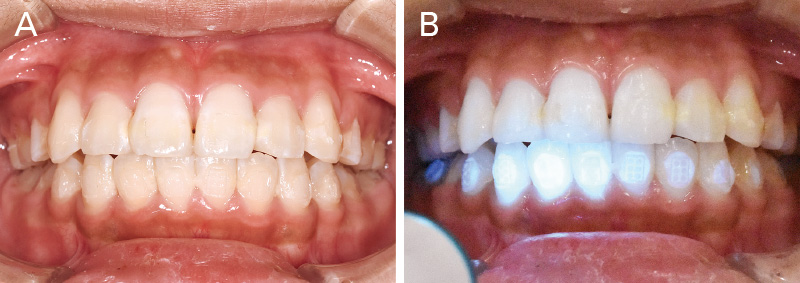

動的治療終了時のブラケット除去について考察する。矯正治療において、接着材の選択は『装置を確実に接着すること』だけでなく、『デボンド時の歯面への負担を最小限に抑えること』も重要である。筆者の臨床では、CR系矯正用接着材と4-META/MMA-TBB系レジン接着材を部位や状況に応じて使い分けている。具体的には、補綴装置へのブラケット接着、一度ブラケットが脱離した部位、大臼歯など防湿管理が難しい部位では、エッチング処理後に「ボンドフィルSBⅡ」を選択している。また、前歯部など審美的要求が高く脱離リスクが比較的低い部位に対しては、「ティースプライマー」処理後に同じく「ボンドフィルSBⅡ」を使用する。一方で、接着難易度が低い下顎前歯部やブラケットのポジショニングに時間を要する小臼歯部では、操作性に優れるCR系矯正用接着材を選択している。筆者の臨床経験から、エナメル質の歯面処理材に「ティースプライマー」を用い、「ボンドフィルSBⅡ」で接着した場合、ブラケット除去時にはレジンの多くがブラケット側に残り、歯面に残るレジン量は比較的少ない(図14A, B)。そのため、歯面に残存するレジン除去の時間を短縮でき、回転切削器具の使用を最小限に抑えることが可能となる。一方、CR系矯正用接着材を用いてブラケットを接着した場合には、デボンド時にレジンが歯面に残るため、その切削除去に多くの時間と慎重な作業を要する。また、「スーパーボンド」や「ボンドフィルSBⅡ」は熱で軟化する性質があるため、弱い圧で効率的に除去が可能であり、レジンリムービングプライヤーによる除去も容易である。

図14A, B デボンド直後のレジン残留状況比較

(上顎:「ティースプライマー」+「ボンドフィルSBⅡ」で接着。下顎:CR系光重合型矯正用接着材で接着)

A:ブラケット除去直後の口腔内写真。上顎前歯は「ティースプライマー」使用

B:下顎は光重合系レジンセメントを使用しており、ブルーライト下で発光している状態。ほとんどのレジンが歯面に残存していることがわかる。 -